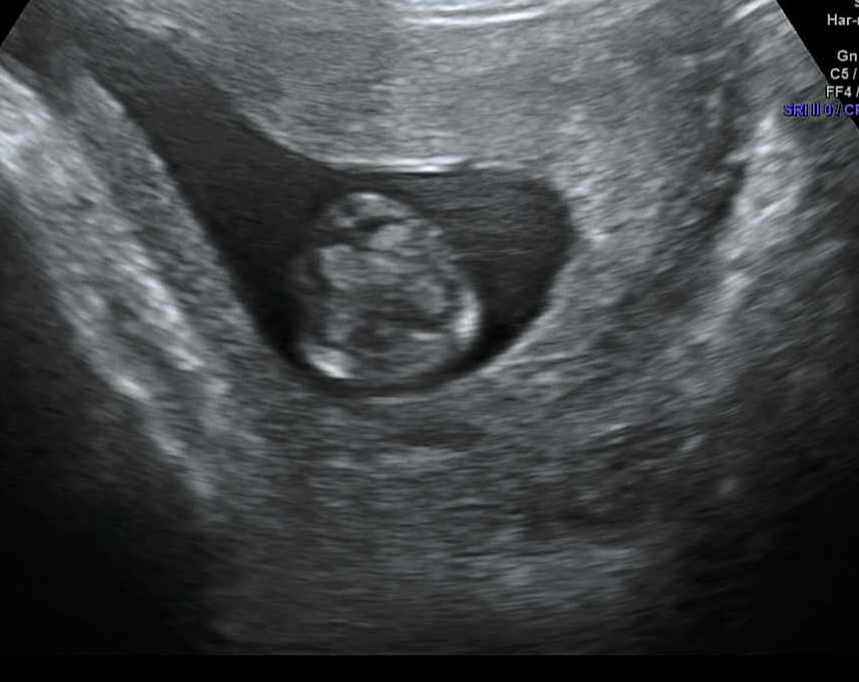

[태아-임신11주 태아 크기 초음파 모습 성별]

-임신11주 태아 초음파

임신11주차 태아 초음파. 왼쪽 사진을 통해 태아의 얼굴의 코, 입, 턱을 확인할 수 있다. 가운데 사진에서 손가락이 5개임을 확인할 수 있다. 마지막 사진을 통해 뇌를 확인할 수 있다. 이 외에도 위, 방광, 척추도 확인 가능하다.